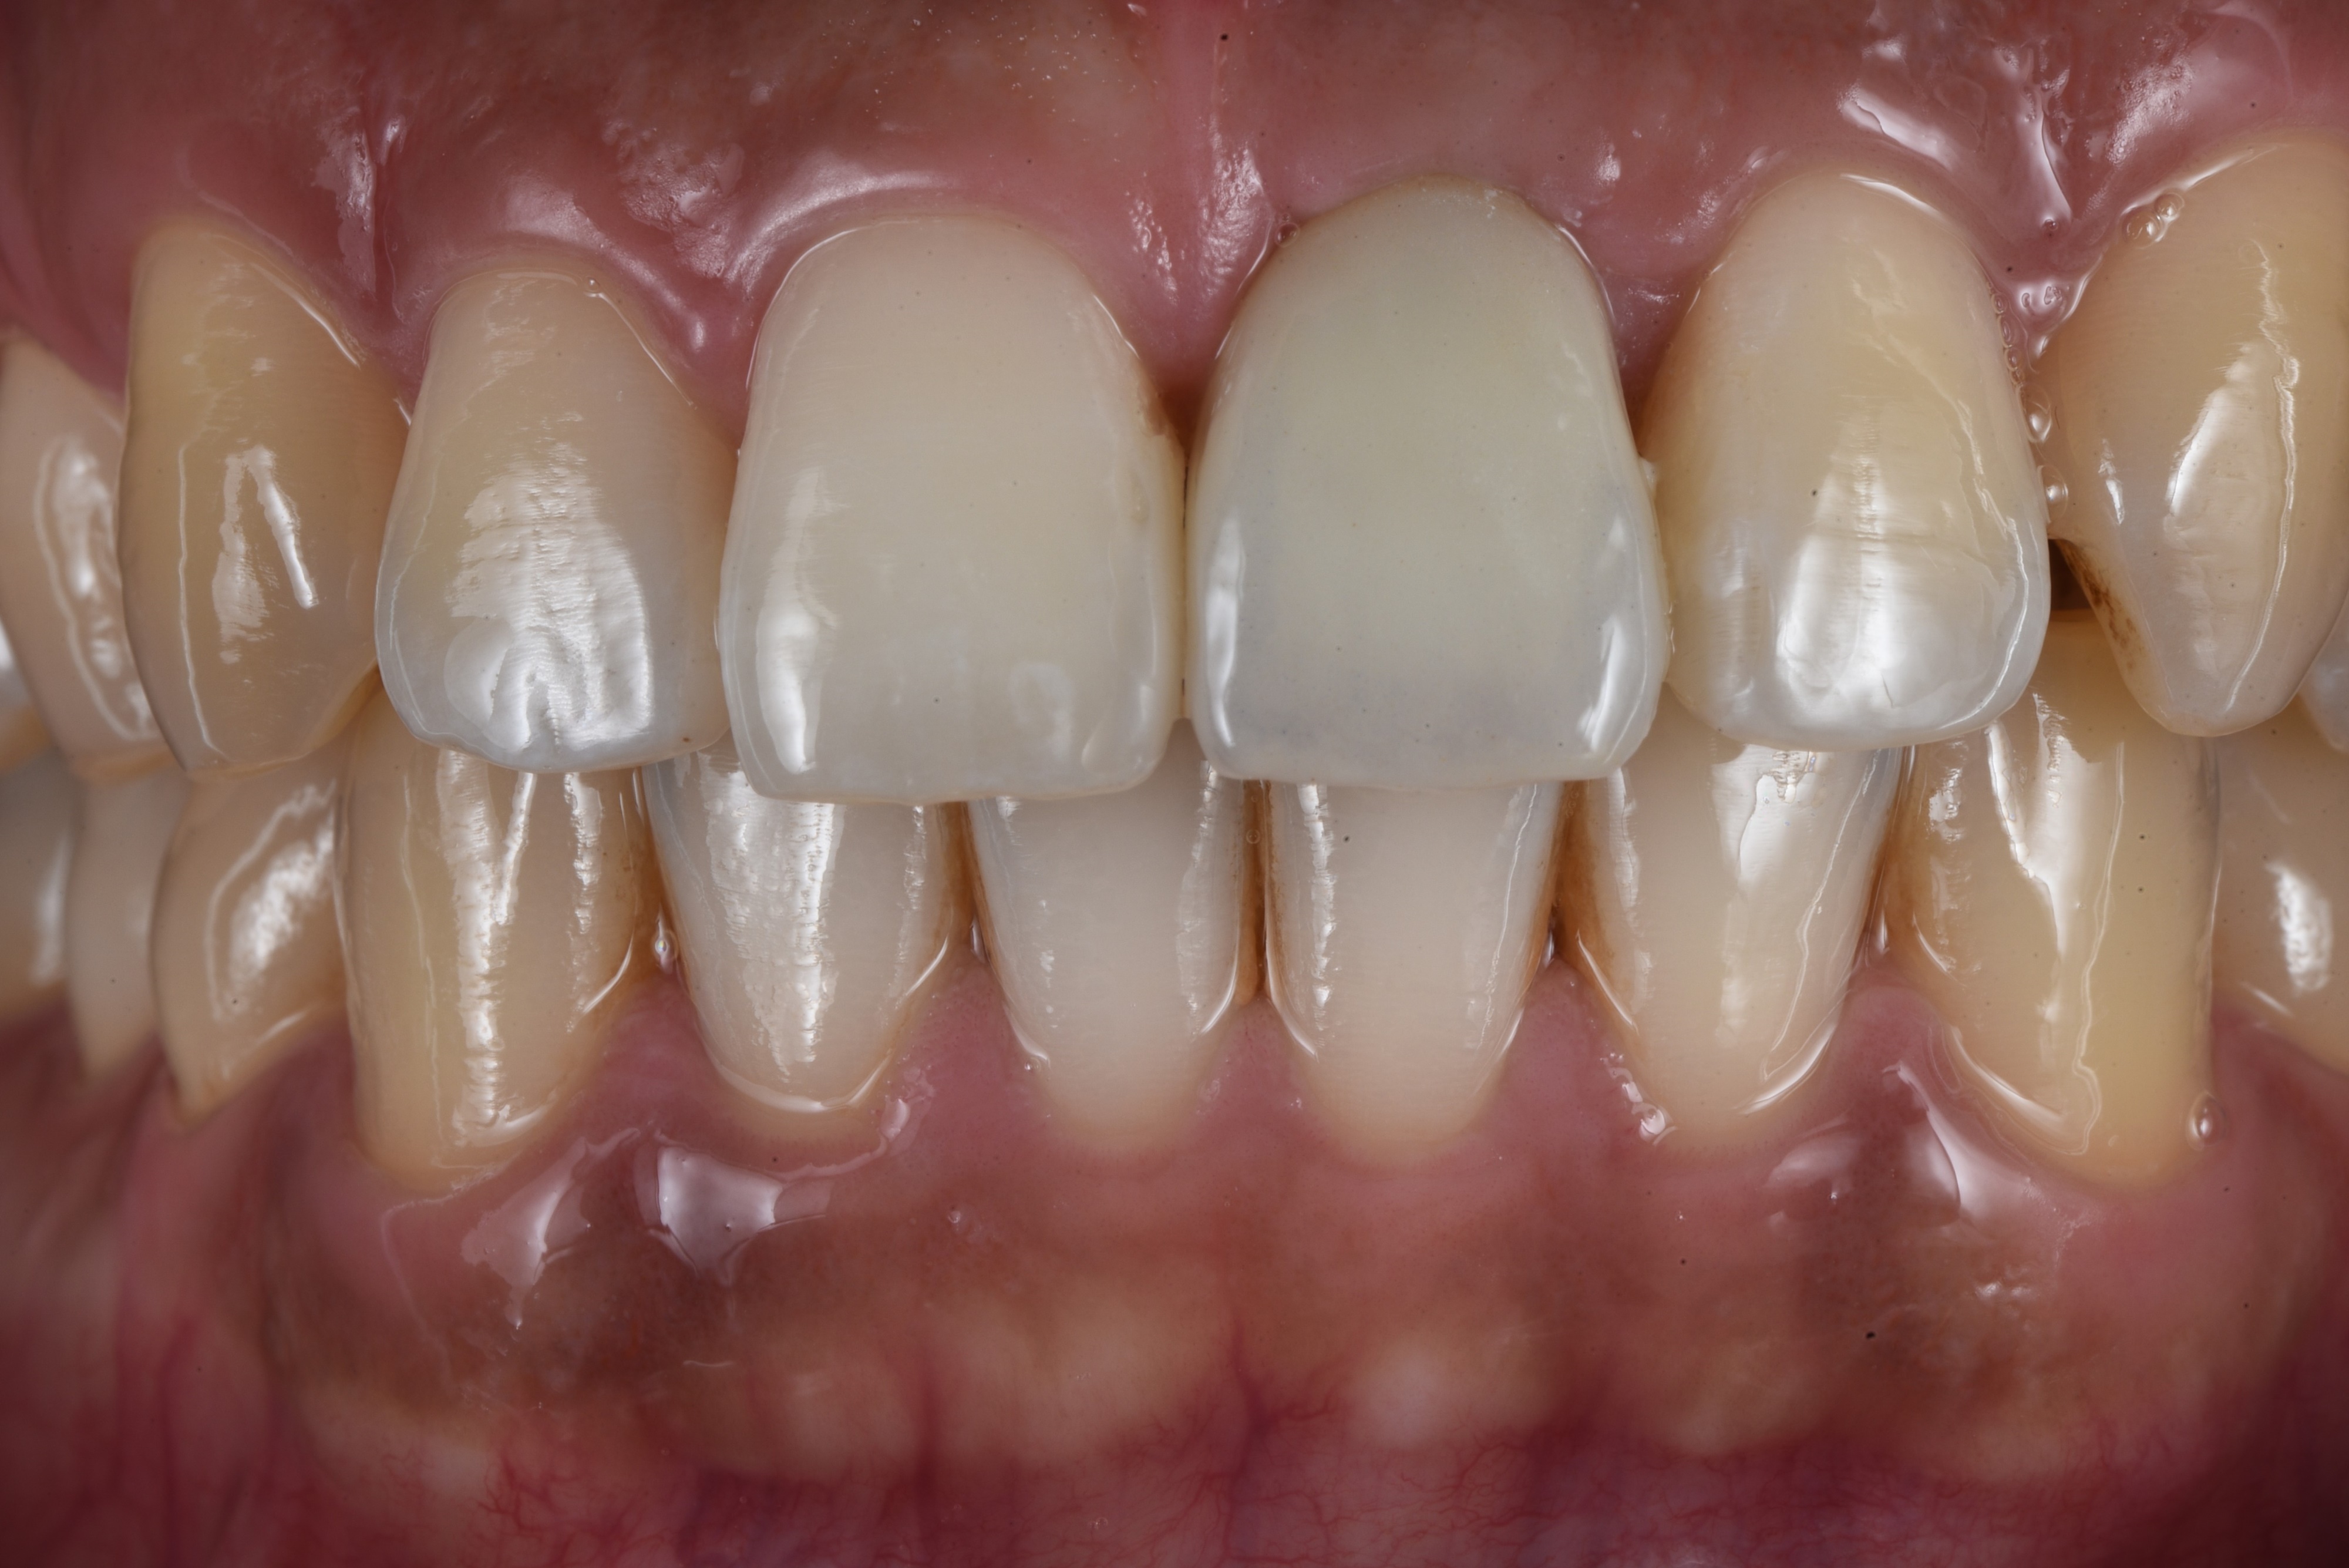

수술 후 임시치아를 먼저 해드렸습니다. 당일 제작한 임시치아는 색상이나 형태가 심미적이지는 않습니다.

<최종 보철>

3개월 후 앞니 임플란트 최종 보철을 마무리 한 사진입니다.